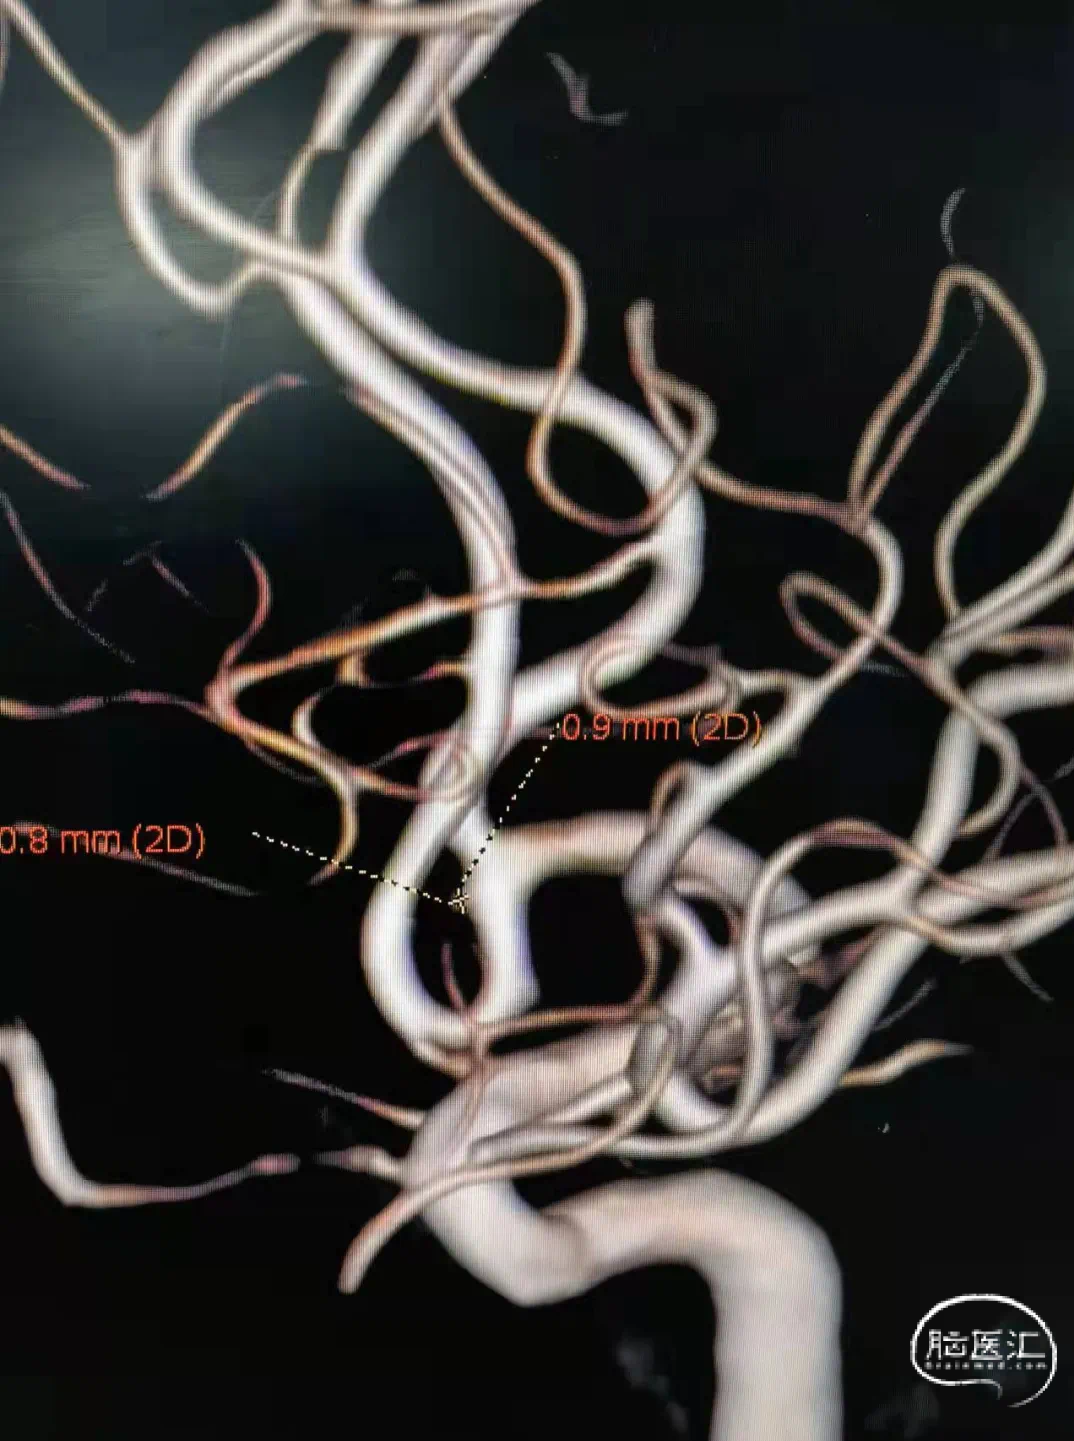

动脉瘤部位:

动脉瘤尺寸:

动脉瘤测量:

动脉瘤特点:

术前影像